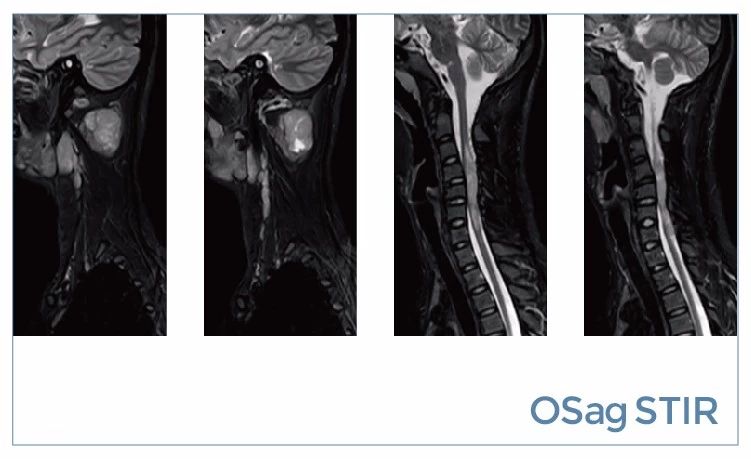

【朗润影像档案】磁共振影像病例分享(编号20190816)